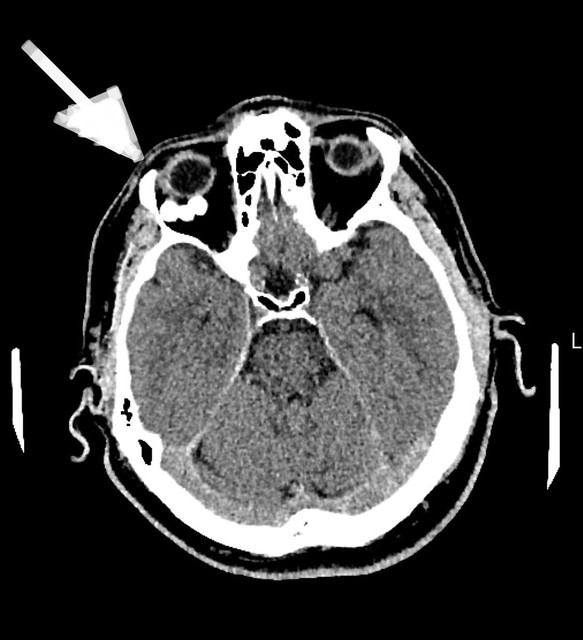

Pirms operācijas / Foto: publicitātes

Padziļināti izmeklējumi atklāja ļoti retu, kalcinētu veidojumu, kas saspieda acs muskuļus un nervus, izraisot neiroloģiskos simptomus.

Operācijas laikā neiroķirurģijas komanda veica augstas precizitātes ķirurģisku iejaukšanos - caur galvaskausu tika izveidota aptuveni 1 cm liela atvere acs dobuma sienā, ļaujot pilnībā izņemt patoloģisko veidojumu, nebojājot acs struktūras.